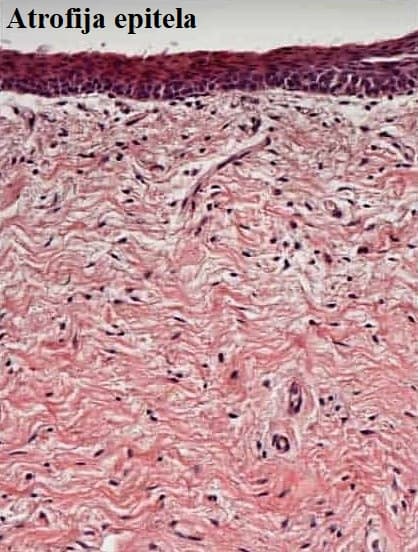

Vaginalna atrofija se odlikuje stanjenjem, sušenjem i upalnim promjenama vaginalnih stijenki, što smanjuje kvalitetu svakodnevnog života stvarajući probleme s mokrenjem, te uzrokuje bolnost pri spolnom odnosu, ali i svakodnevnim aktivnostima. Samo manji broj žena pripisuje simptome hormonskim promjenama, većina žena se ne konzultira s ginekologom o svojim simptomima, smatrajući ih dijelom normalnog starenja. Također, određeni broj žena još uvijek nije spreman uzimati hormonsko nadomjesno liječenje zbog zabrinutosti zbog štetnih učinaka uključujući karcinom.